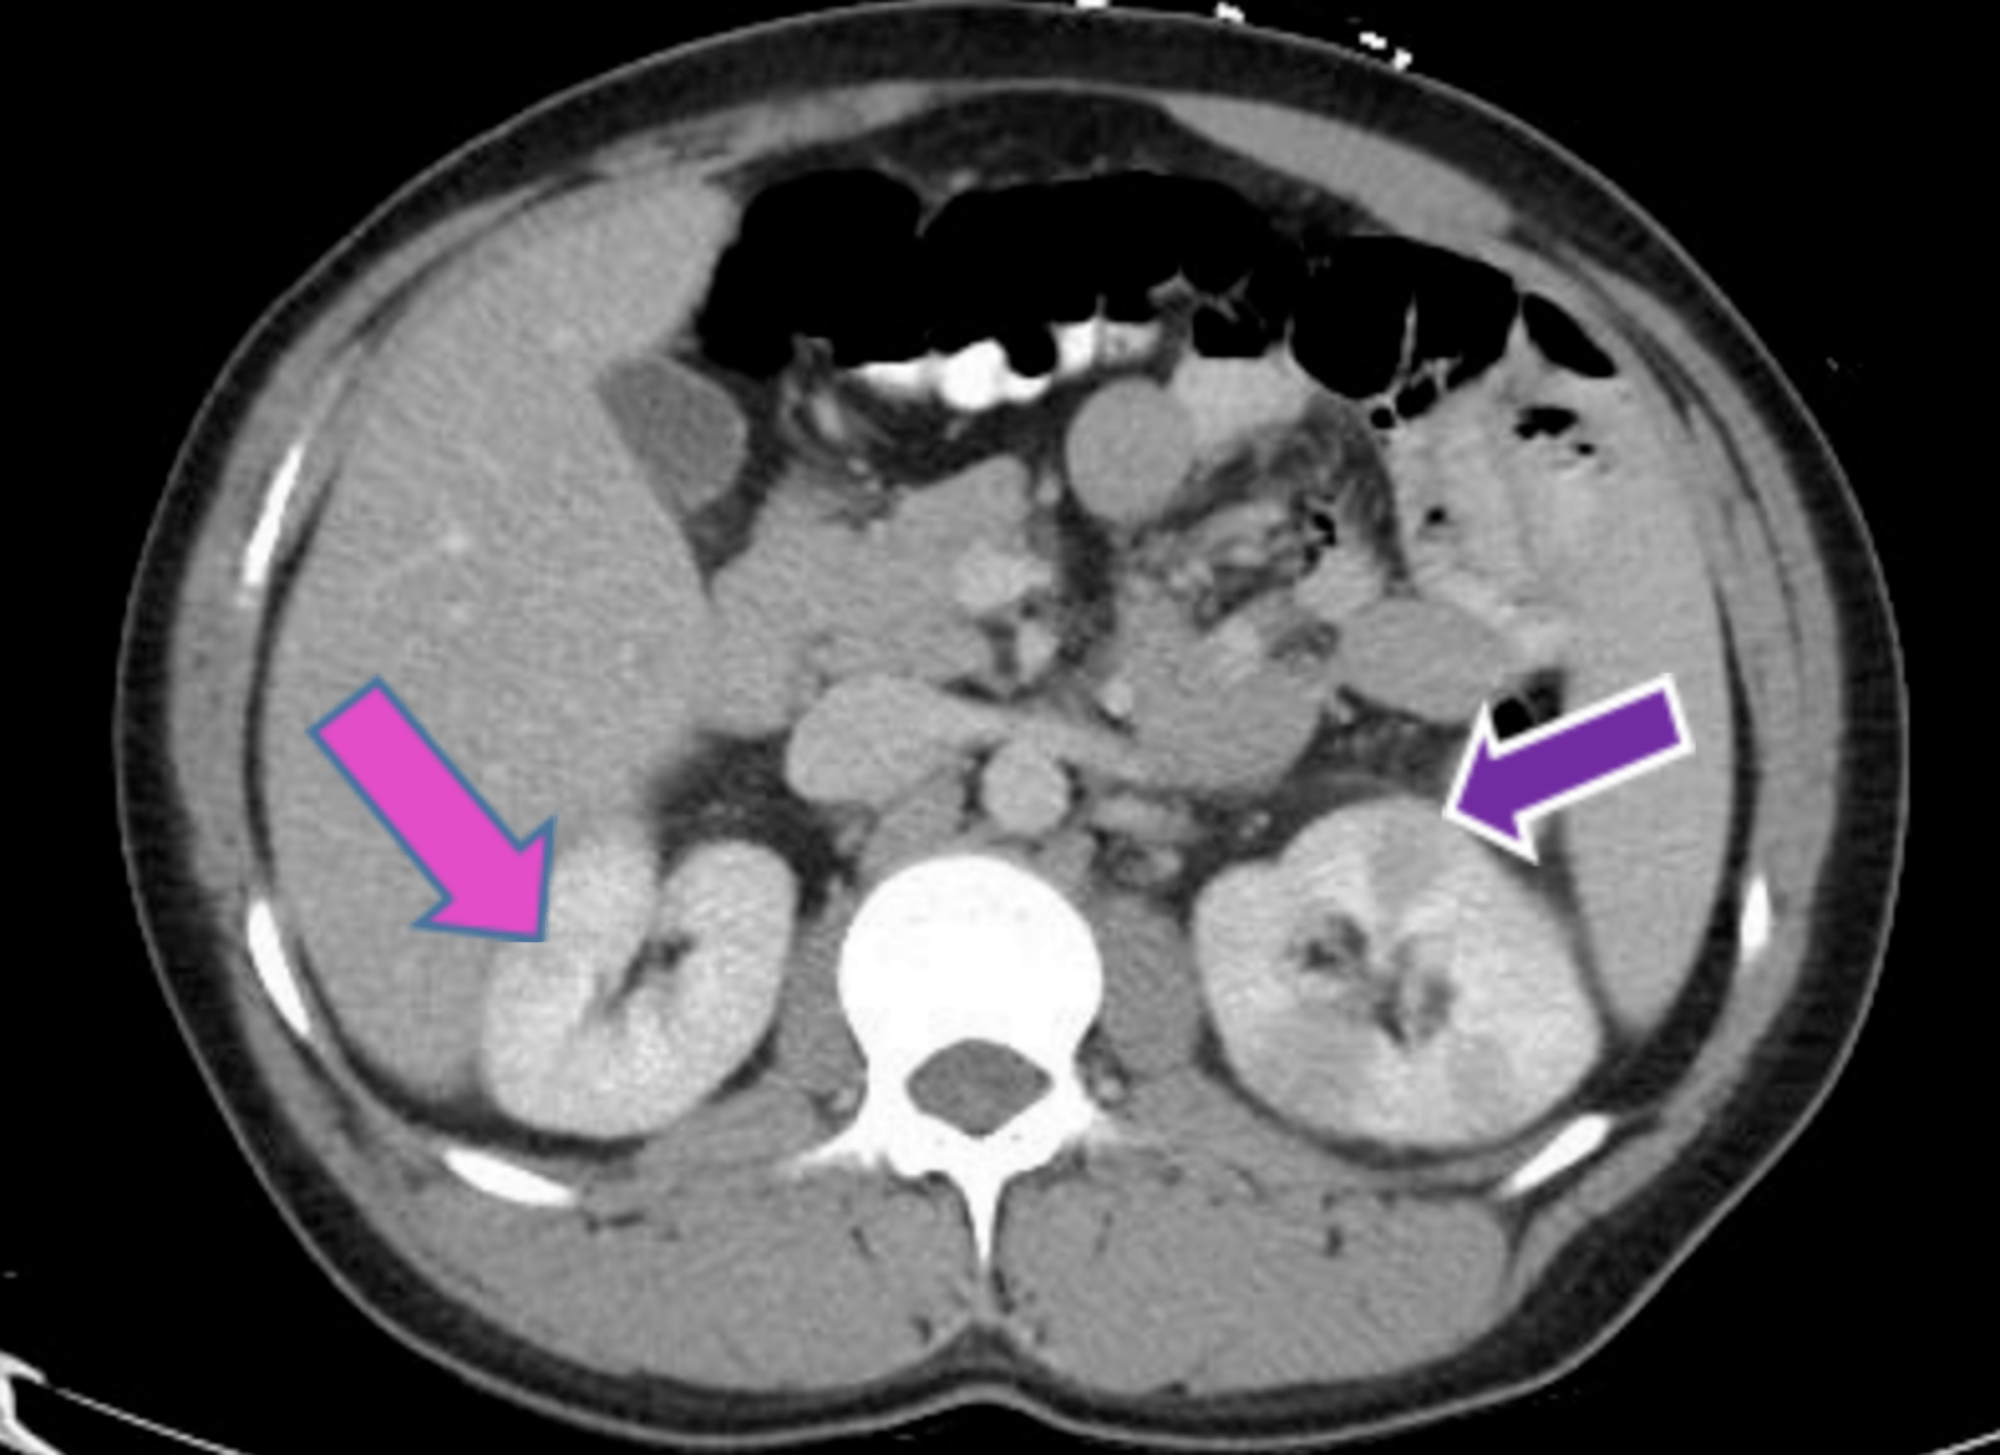

Urinary complications in Crohn’s disease and ulcerative colitis Crohn's Disease And Urinary Problems Urological complications of crohn's disease are rare, often asymptomatic and present a diagnostic problem. People diagnosed with crohn’s disease have a higher risk of developing kidney stones in the urinary tract than those without crohn’s, including those with ulcerative colitis. Cystitis was the most common. Crohn’s disease can also cause. Any feedback would be so helpful. Has anyone ever had. Crohn's Disease And Urinary Problems.